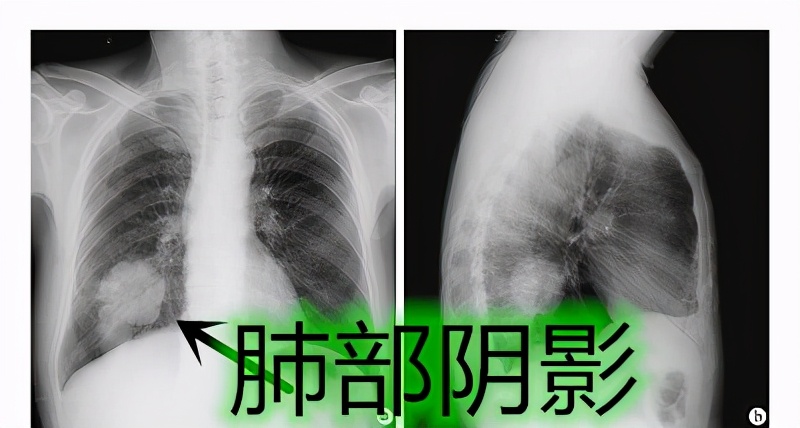

其实我们说的肺部阴影和肺结节都是影像科的术语。在x光透过人体时, 光 会被密度 较大的组织 给抵挡住,从而在底片上留下影子。但与一般的影子不同 , x光的阴影是白色的 。如下图所示。这就好解释了,只要是你肺部的 组织变得不均匀 ,就可能导致阴影或者结节出现。所以一旦出现了肺部阴景肺结节,就意味着肺部有不同于正常组织的东西。那么阴影和结节有什么区别呢?其实这是一种物质,只不过大小不同,叫法不同罢了。当这个肺部长了一个东西,这个东西的 直径小于3公分(3cm )我们称之为结节。当然结节又进行了细分, 小于2公分 我们称之为小结节,而 小于1公分 我们称之为微小结节。当这个东西 大于3公分 的时候,我们才称之为 阴影或者肿块, 由此可见阴影更大。相对来说危险也就更大了。